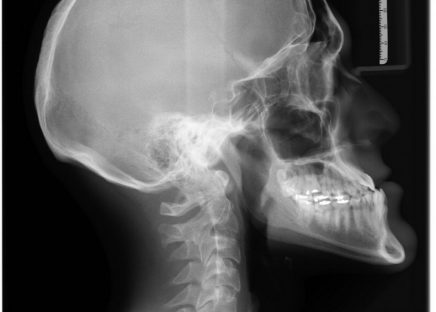

Røntgenundersøgelse: En vej til en sundere krop

Røntgenundersøgelser spiller en væsentlig rolle i moderne medicinsk diagnostik, og de hjælper læger med at identificere og behandle en bred vifte af helbredsproblemer. Denne artikel vil give en indsigt i, hvordan r&osl...